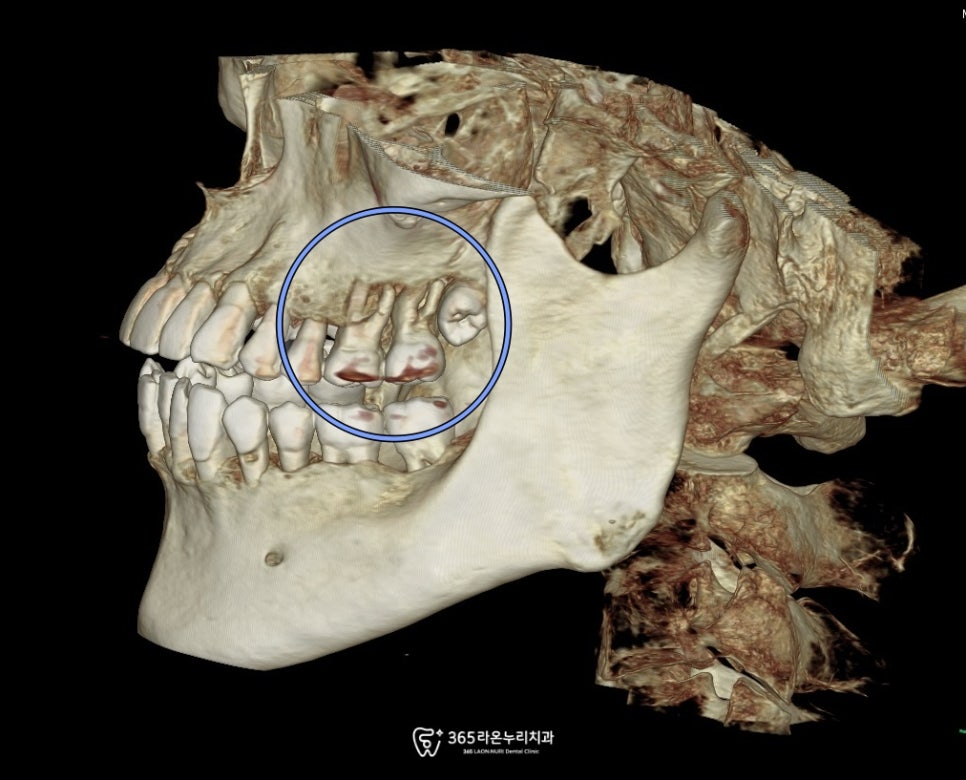

치아의 뿌리주변으로

뼈소실이 진행되고

변성된 조직이 있다면,

더 이상 주변의 뼈를 소실시키지 않도록

감염원을 모두 드러내는

발치를 해주는 것이

다른 치아들을 보존 할 수 있는

치료 방법이 됩니다.